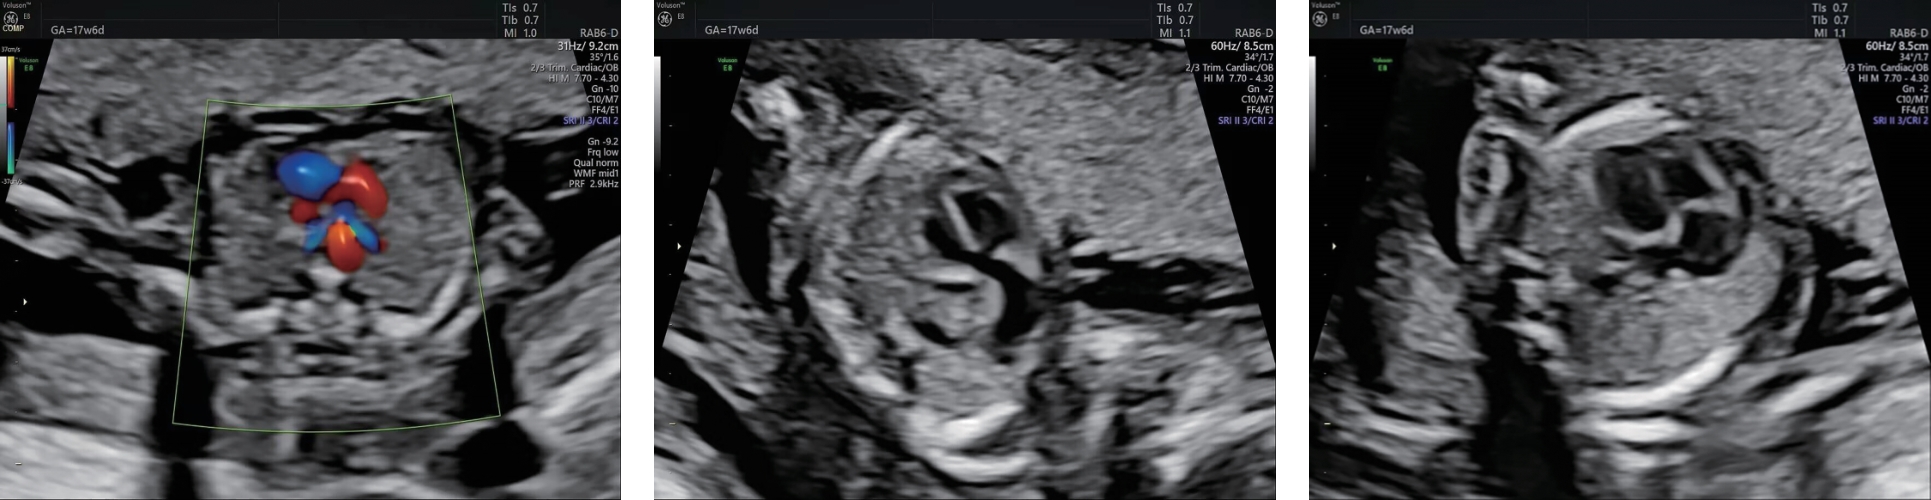

• 孕中期超声多切面检查对超重孕妇胎儿心脏畸形的诊断价值

2026, 36(4):72-77. DOI: 10.3969/j.issn.1005-8982.2026.04.012

摘要 (49) HTML (61) PDF 2.01 M (32) 评论 (0) 收藏

摘要:目的 分析孕中期超声多切面检查对超重孕妇胎儿心脏畸形的诊断价值。方法 回顾性分析2023年6月—2024年12月在商洛市中心医院超声医学科进行孕中期心脏超声检查的114例超重孕妇的临床资料,所有孕妇行超声常规和超声多切面检查,分别在平卧位、侧卧位下完成检查,以随访结果为金标准,分析超声多切面检查的诊断效能及图像质量。结果 超声多切面检查平卧位和侧卧位图像满意度均高于超声常规检查(P <0.05);侧卧位超声多切面检查和超声常规检查图像满意度均高于平卧位(P <0.05)。随访结果显示,5例(4.39%)心脏畸形胎儿中,室间隔缺损1例、三尖瓣下移畸形2例、左心发育不良1例、单心室1例。超声常规检查的敏感性为20.0%(1/5),特异性为92.7%(101/109),准确度为89.5%(102/114);超声多切面检查的敏感性为80.0%(4/5),特异性为97.2%(106/109),准确度为96.5%(110/114);两者联合检查的敏感性、特异性、准确度均为100.0%。孕22~<24周的52例孕妇中,检出心脏畸形1例(1.92%),孕24~<26周的62例孕妇中,检出心脏畸形4例(6.45%)。结论 孕中期超声多切面检查可显著提高超重孕妇胎儿心脏畸形的检出准确性,图像质量优于超声常规检查。联合多切面与常规超声检查可使敏感性、特异性及准确度均达100%,推荐作为超重孕妇胎儿心脏畸形筛查的优选方案。

• 0+1

• 1+1

• 2+1